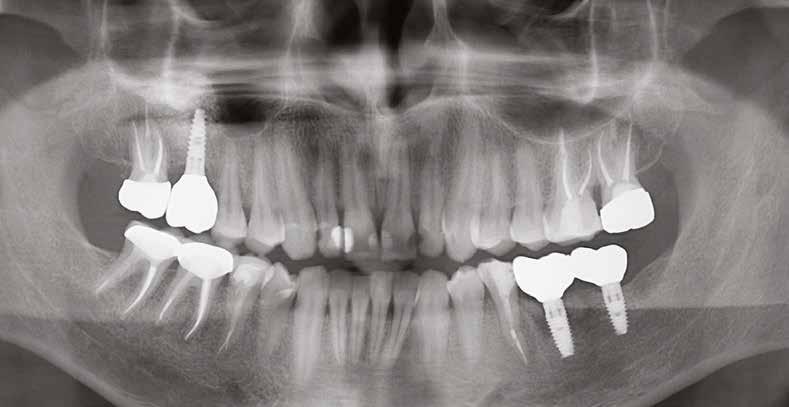

3. a–b ábra: Röntgenfelvételek három hónap után (a) és a gyógyulási csavarok behelyezve (b, 1. eset).

4. a–b ábra: Röntgenfelvételek öt hónappal később (a) és a gyógyulási csavarok behelyezve (b, 2. eset).

5. a–c ábra: Röntgenfelvételek öt hónappal később (a) és a gyógyulási csavarok behelyezve (b és c, 3. eset).

6. a–b ábra: Röntgenfelvételek öt hónappal később (a) és a gyógyulási csavarok behelyezve (b, 4. eset).

8. a–b. ábra: Végső röntgenfelvétel az implantátum helyzetéről (a) és a szájon belüli végső szituáció az 1. esetről (b).

9. a–b. ábra: Végső röntgenfelvétel az implantátum helyzetéről (a) és a szájon belüli végső szituáció a 2. esetről (b).

10. a–c. ábra: Végső röntgenfelvétel az implantátum helyzetéről (a) és a szájon belüli végső szituáció a 3. esetről (b és c).

tottuk (az okklúziós koncepciók alapján az implantációs pótlások nem voltak vezető fogak, és csak könnyű érintkezéseket alakítottunk ki, amelyeket artikulációs papírral ellenőriztünk). A páciensek instrukciókat kaptak a megfelelő szájhigiénére vonatkozóan, összpontosítva a fogköz kefékkel történő tisztítására. Végső kontroll röntgenfelvétel készült. A PEEK felépítmény nem radioopák, így az implantátum és a korona közötti távolság könnyen meghatározható a röntgenfelvételen: a felépítmény megfelelően illeszkedik az implantátumban, ha az implantátum válla és a korona alsó széle közötti rés 0,55 mm a röntgenfelvételen (8–11. ábra)

11. a–b. ábra: Végső röntgenfelvétel az implantátum helyzetéről (a) és a szájon belüli végső szituáció a 4. esetről (b).